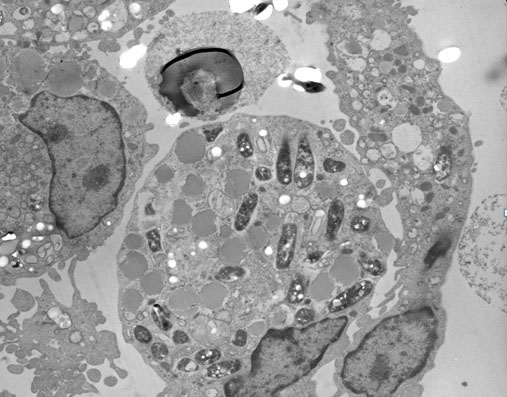

To replicate granuloma formation in an in vitro model, we infected human PBMCs with M. tuberculosis H37Ra or BCG and incubated for 5 days. At 24 h of incubation, PBMCs tended to form cellular aggregations of lymphocytes in the presence of H37Ra (Fig. 1A) or BCG (Fig. 1B). Corresponding control samples from the same donors cultured in the presence of Escherichia coli ATCC 25922 or Staphylococcus aureus ATCC 25923, or cultured in the absence of bacteria did not form these aggregates (Figs 1C, 1D, 1E) indicating that cellular aggregation forms specifically in response to M. tuberculosis infection. The granuloma-like shape of the cell aggregates formed following 24 h of M. tuberculosis H37Ra infection was confirmed by Wright-Giemsa staining (Fig. 1F). Transmission electron microscopy evidenced the engulfment of mycobacterial cells by phagocytes present in the cellular aggregates at 48 h post-infection (Fig. 2). The in vitro granulomatous structures persisted for 96 h, and then began to disappear.

Figure 2.

Transmission electron microscopy of H37Ra-induced granuloma. After 48 hour post-infection, cellular aggregations were collected, fixed and embedded in an Epon-araldite resin. Sections of 0.5 µm were obtained, stained and observed under transmission electron microscope (4,000x). Multiple phagosomal vesicles containing H37Ra bacteria can be observed.